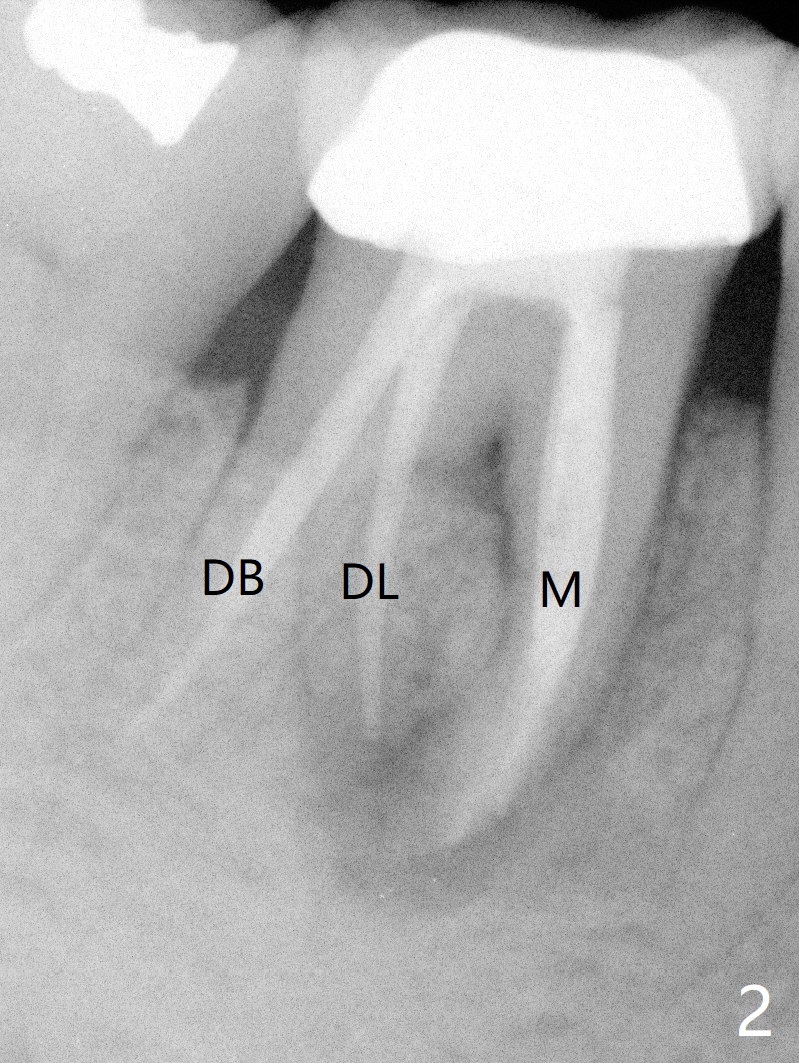

A 55-year-old woman has severe bone loss (Fig.1 with buccal and lingual fistulae) around the mesial (M in Fig.2) and distolingual (DL) roots. If there is a septum after extraction (Fig.3 S), osteotomy will be established in the septum to enhance primary stability (Fig.4). When the septum cannot be saved (Fig.5), osteotomy is to be initiated in the septal slope oblique (Fig.6 <). The osteotomy will be straightened once an entry is made (Fig.7). The initial osteotomy is slightly distal, since as osteotomy increases (Fig.8 blue), it tends to shift mesial (arrow). In addition, the apex of the 2nd bicuspid tilts distal (yellow dashed line). Depth of osteotomy is 20 mm (crest, Fig.9) or 18 mm (septum) so that 8 mm of the native bone can be obtained with 3 mm clearance from the Inferior Alveolar Canal (red dashed line). PRFx2 is required (seems not done).